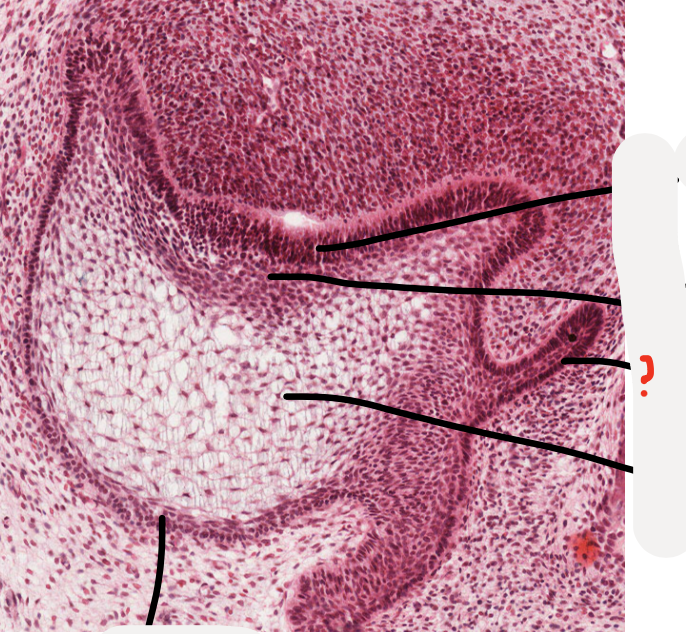

3

Q

A

dental lamina

How well did you know this?

1

Not at all

2

4